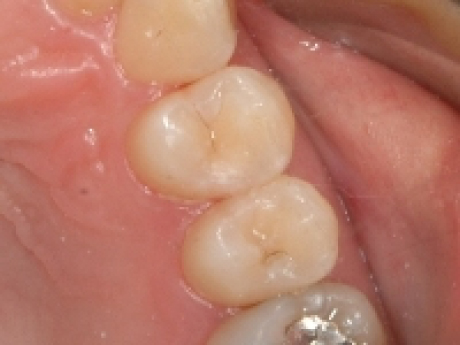

case1